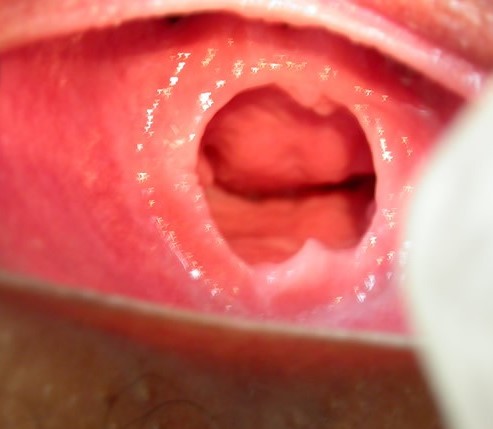

- ACTO CONTRANATURA RECIENTE: SE APRECIA UN ORIFICIO ANAL QUE HA PERDIDO SU FORMA ANATOMICA, CON TUMEFACCION Y EQUIMOSIS DE PLIEGUES PERIANALES, PRESENCIA DE HEMATOMA A HORAS XI-XII, FISURA ANAL A HORAS VI.